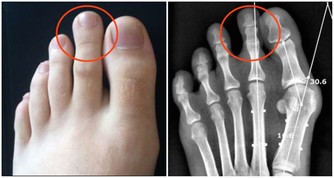

***5.潤滑關節。***蹲姿通過下肢有規律的折疊,對關節周圍組織是一種很好的伸展鍛煉,對膝關節和髖關節尤其適用。

***7.鍛煉下肢肌肉。***有針對性地做下蹲鍛煉,可增強膝關節穩定性和下肢肌肉力量,進而促進速度、爆發力、耐力的提升,同時健美大腿和臀部。